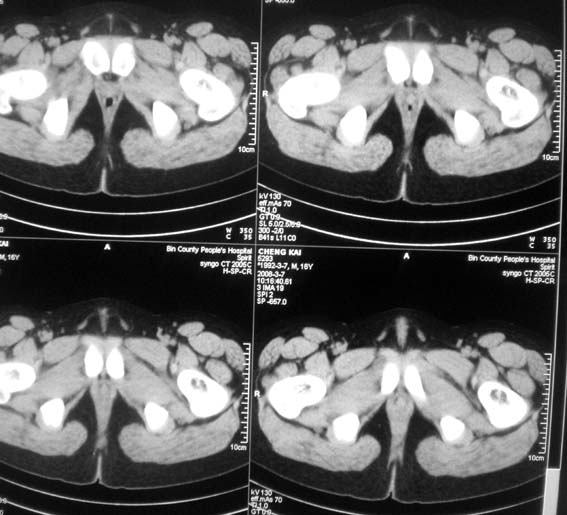

标题: CT12101:髋关节疼痛,请会诊。

男,16岁,髋部疼痛,发育延迟。

考虑:双侧髋臼发育不良性骨病。

双侧髋臼发育不良性骨病

双侧髋臼发育不良性骨病.股骨头早期坏死?

双侧髋臼发育不良性骨病(髋臼窝变浅,髋臼内上缘关节面毛糙)。

考虑:双侧髋臼发育不良性骨病